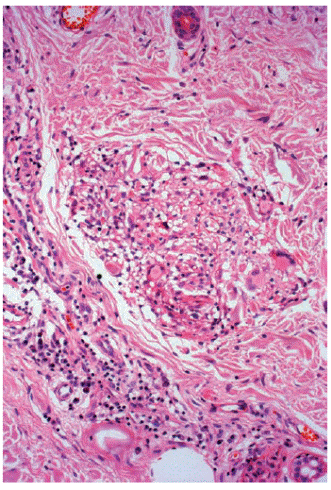

Figura 5 Granuloma de macrófagos vacuolados, células epitelioides, algunas gigantes, linfocitos y plasmocitos, en los bordes laterales de la lesión. Hematoxilina y eosina, 20X.